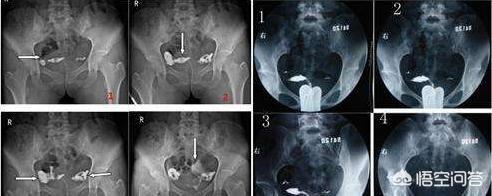

【子宫输卵管造影】是指系通过子宫颈管向子宫腔内注入由造影剂,经X线摄片,了解子宫及输卵管情况的一种检查。因操作简便、迅速,诊断准确率高,副作用低,是检测输卵管功能的重要方法。